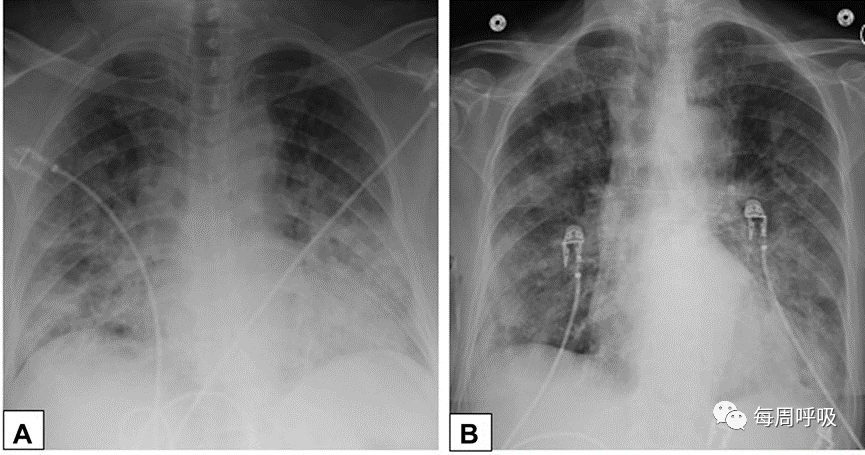

在病变主要是OPP的病例中,应评估活检标本是否有提示SOP潜在病因的特征,如显著的慢性间质性炎症(药物毒性、胶原血管疾病[图22])或放射性肺炎。最后,OPP必须与其他ILD相区别,尤其是DAD的机化期,该期表现为明显的腔内出芽纤维化,与OPP相似。DAD与OPP的区别在于肺受累呈弥漫性而非斑片状(图25A、25B),常伴有反应性细胞异型性(图25B)、机化性纤维化导致间质增厚(图25A、25B)、透明膜(图25A)和/或急性炎症和出血灶。与DAD患者不同,COP患者通常可游走,胸部影像学显示如上所述的斑片状结节性浸润(图26)。

图25机化性肺炎(OPP)的鉴别诊断A,弥漫性肺泡损伤OPP。该活检标本显示弥漫性累及机化结缔组织,导致肺泡壁增厚(厚箭头)和相关透明膜(薄箭头),由密集的粉红色透明渗出物组成,沿肺泡壁表面排列。B,除了疏松的结缔组织导致肺泡壁增厚(粗箭头)外,还有明显的肺细胞增生伴一些不典型特征(细箭头)。C,鳞癌旁OP。鳞状细胞癌周围的肺实质(粗箭头)包含OPP区域(细箭头)。鳞状细胞癌由具有角化特征的肿瘤细胞巢组成(插入图片)。D, OP由远端气道内疏松结缔组织构成的息肉样栓子(箭头所示),类似于隐源性OP或继发性OP。E,梗死周围的OP。梗死灶由圆形的嗜酸性死肺组织(粗箭头)组成。它被纤维炎症反应包围,有明显的OP成分(曲线箭头)。F, 缩窄性细支气管炎(也叫闭塞性细支气管炎)。图示细支气管的同心圆纤维化层(箭头所示)位于上面的呼吸道黏膜和下面环绕细支气管的正常平滑肌之间。这种纤维化引起细支气管腔明显狭窄。

图26弥漫性肺泡损伤和机化性肺炎。一名经活检证实弥漫性肺泡损伤的66岁女性患者的正位胸片(a)显示双侧弥漫性实变,一名经活检证实的机化性肺炎的37岁男性患者(B)显示双侧斑片状、结节状阴影。